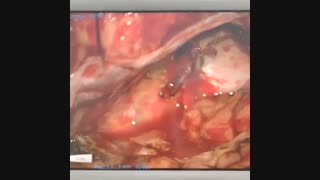

پخش صدا عمل جراحی تومور مننژیوم اشتراکگذاری لیست پخش ۰ نظر ۰ نظر دانلود دانلود ویدیو دانلود کیفیت 720p ۱۸.۷۹ مگابایت دانلود کیفیت 480p ۱۳.۱۰ مگابایت دانلود کیفیت 360p ۹.۰۲ مگابایت دانلود کیفیت 240p ۵.۶۰ مگابایت دانلود کیفیت 144p ۳.۲۵ مگابایت گزارش تخلف بیشتر گزینههای بیشتر لیست پخش لایکها گزارش تخلف ۰ لایک دکتر محمد صمدیان منتشر شده در تاریخ ۱۴۰۰/۱۲/۱۲ این کانال دنبال شد دنبال کردهاید دنبال کردن این کانال دنبال کردن جهت کسب اطلاعات بیشتر به سایت مراجعه بفرمایید:https://drsamadian.com/j,l, ادامه علم و فن آوری نظرات لبخند لبخند لغو ثبت نظری برای نمایش وجود ندارد.